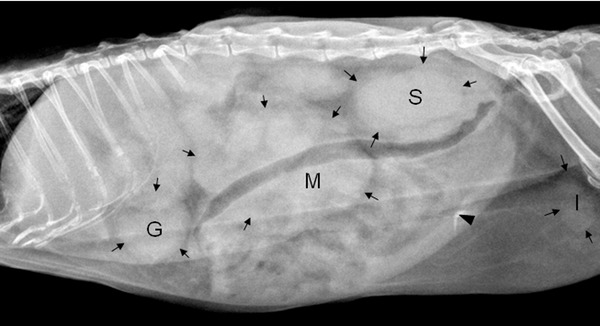

Если в ходе проведенных лабораторных анализов определяется доброкачественное новое образование, то оно быстро удаляется путем хирургического вмешательства. В случае злокачественной лимфомы обследование продолжают назначением рентгена и УЗИ внутренних органов на предмет метастазов, после чего проводят операцию по удалению опухолевых образований.

| Диагностика | УЗИ брюшной полости, рентген, биопсия (тонкоигольная аспирация, хирургическая), анализы крови | Высокая, для подтверждения диагноза и определения стадии |